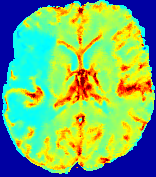

LesionRefer to captionRefer to captionRefer to captionRefer to captionRefer to captionRefer to caption𝐕rgbsubscript𝐕𝑟𝑔𝑏{\bf{V}}_{rgb}Refer to captionRefer to captionRefer to captionRefer to captionRefer to captionRefer to caption𝐕2subscriptnorm𝐕2{\|\bf{V}}\|_{2}Refer to captionRefer to captionRefer to captionRefer to captionRefer to captionRefer to captionRefer to caption3.53.53.52.82.82.82.12.12.11.41.41.40.70.70.70.00.00.0(mm/s)𝑚𝑚𝑠(mm/s)D𝐷DRefer to captionRefer to captionRefer to captionRefer to captionRefer to captionRefer to captionRefer to caption0.0200.0200.0200.0160.0160.0160.0120.0120.0120.0080.0080.0080.0040.0040.0040.0000.0000.000(mm2/s)𝑚superscript𝑚2𝑠(mm^{2}/s)Slice #1Slice #2Slice #3Slice #4Slice #5Slice #6

Figure 3: PIANO feature maps for one stroke patient, where the lesion is located in the left hemisphere. Top row: segmented stroke lesion region (white) on different slices, obtained from ISLES 2017. The corresponding slices for the PIANO feature maps are shown in the following rows.

For a better insight into an estimated velocity field 𝐕𝐕{\bf{V}} and diffusion field 𝐃𝐃{\bf{D}}, we compute the following maps: (1) 𝐕rgbsubscript𝐕𝑟𝑔𝑏{\bf{V}}_{rgb}: Color-coded orientation map of 𝐕=(Vx,Vy,Vz)T𝐕superscriptsuperscript𝑉𝑥superscript𝑉𝑦superscript𝑉𝑧𝑇{\bf{V}}=(V^{x},V^{y},V^{z})^{T}, obtained by normalizing 𝐕𝐕{\bf{V}} to unit length and mapping its 3 components to red, green, blue respectively; (2) 𝐕2subscriptnorm𝐕2\|{\bf{V}}\|_{2}: 222 norm of 𝐕𝐕{\bf{V}}; (3) D𝐷D: scalar field in Eq. 5.

Fig. 3 and Fig. 4 show the PIANO feature maps estimated from two ISLES 2017 patients: all are highly consistent with the lesion in both cases. Details of the blood flow trajectories are revealed in 𝐕rgbsubscript𝐕𝑟𝑔𝑏{\bf{V}}_{rgb} by the ridged patterns and the sharp changes of colors in the unaffected (right) hemisphere, while the flat patterns appearing within the lesion provide little directional information about the velocity and indicate low velocity magnitudes. Velocity magnitudes are more directly visualized via 𝐕2subscriptnorm𝐕2\|{\bf{V}}\|_{2}, from which one can easily locate the lesion where 𝐕2subscriptnorm𝐕2\|{\bf{V}}\|_{2} is low. D𝐷D also indicates lower diffusion values in the lesion, though with less contrast potentially due to the fact that it captures the accumulated effect of CA diffusion at the voxel-level.